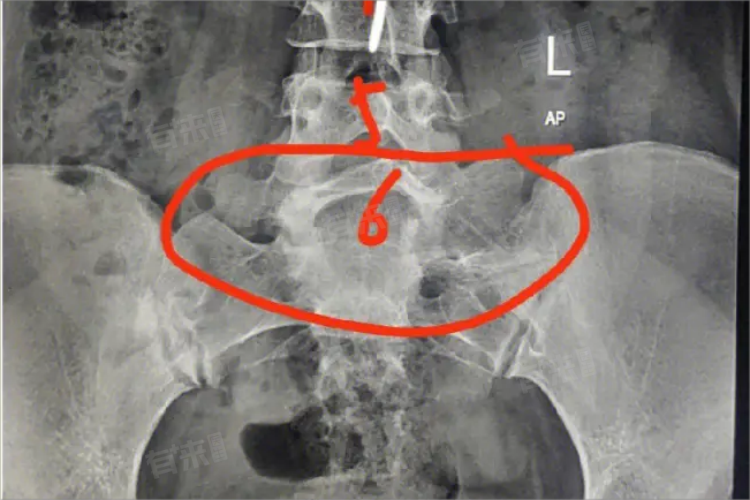

4、诊断与治疗:骶化诊断主要依据X线平片检查,对于伴有腰骶部畸形腰痛患者,需排除其他疾患后方可考虑系畸形所致。对于症状较轻者通常采用保守治疗,如物理治疗、腰背肌功能锻炼、腰围及止痛药物等。症状严重者则需考虑手术治疗,如椎板或椎体融合术等。